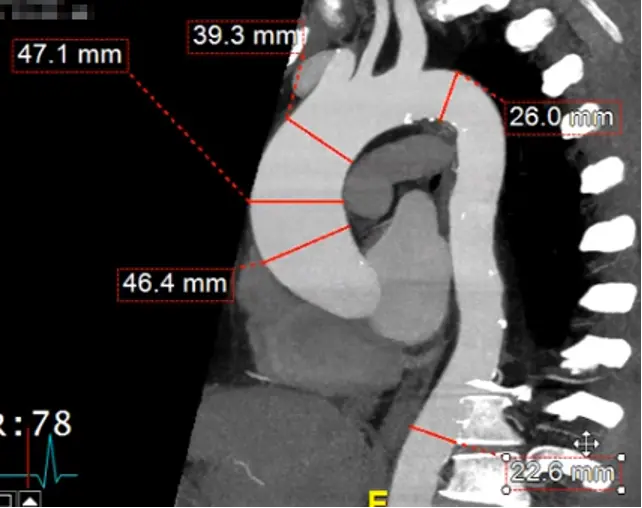

Measure the proximal descending thoracic aorta

- Note: the proximal descending thoracic aorta begins immediately distal to the great vessels (not when the aorta physically starts descending), i.e. after the takeoff of the L subclavian artery

- Line things up in two of the views. In the example Adam showed, he lined it up in the axial and sagittal views and made the measurement in the coronal view.

- Note: the shape of the proximal descending thoracic aorta will not be perfectly circular.

Measure aorta using âcandy caneâ view

- Rotate your cross hairs so you are cutting through both the ascending and descending thoracic aorta.